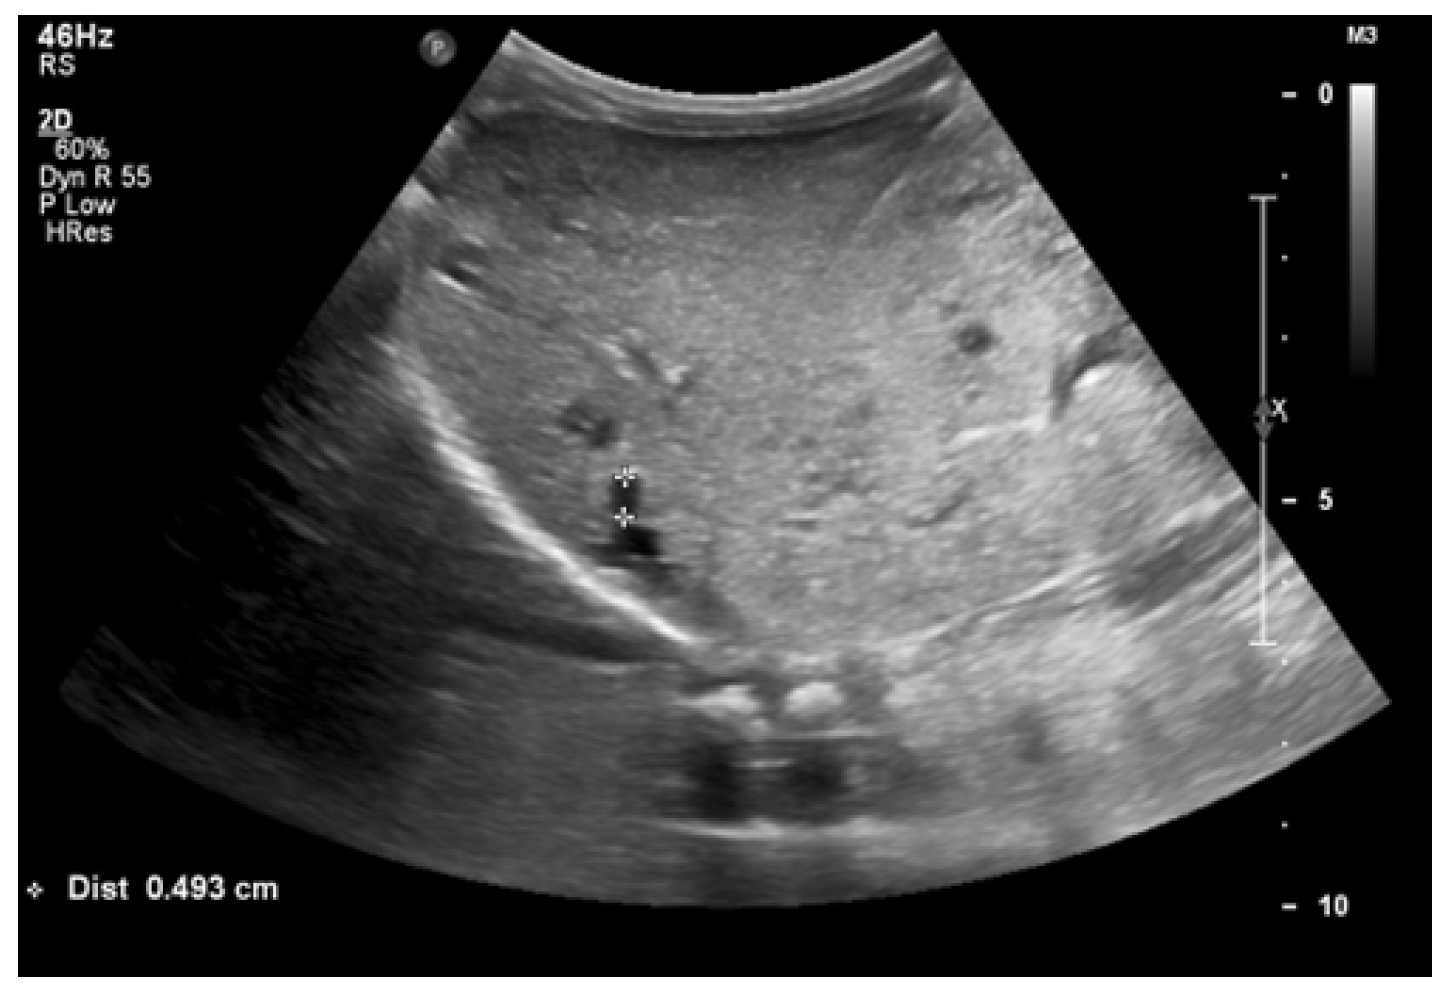

At 4 months of age, the boy was admitted to the hospital due to a hypertensive crisis (BP 162/128 mmHg). Chest X-ray demonstrated cardiomegaly, and echocardiography (ECHO) showed a significant left ventricular hypertrophy and impaired contractility. Abdominal US detected increased kidneys length (right: 101 mm (z-score 8.72); left: 90 mm (z-score 6.59)), with increased echogenicity and loss of corticomedullary differentiation, as well as numerous cysts 5–6 mm in diameter. The liver was enlarged with increased echogenicity with cysts 6–8 mm in diameter (

Figure 1 and

Figure 2). Doppler US demonstrated high-resistance intrarenal blood flow (RI: 0.75–0.84). Laboratory tests showed microcytic anemia, renal function was assessed as serum creatinine, the glomerular filtration rate (GFR) was estimated according to the Schwartz formula, and liver function was all normal. The boy received multi-drug therapy to control hypertension and heart failure. ECHO, performed after 6 months, was correct.